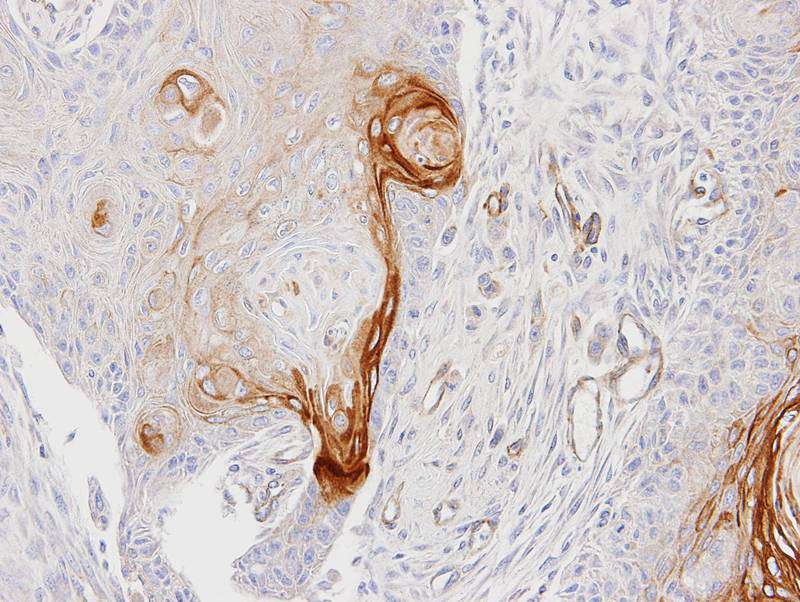

Immunohistochemical analysis of paraffin-embedded Ca922 xenograft, using ENTPD6 antibody at 1: 100 dilution.